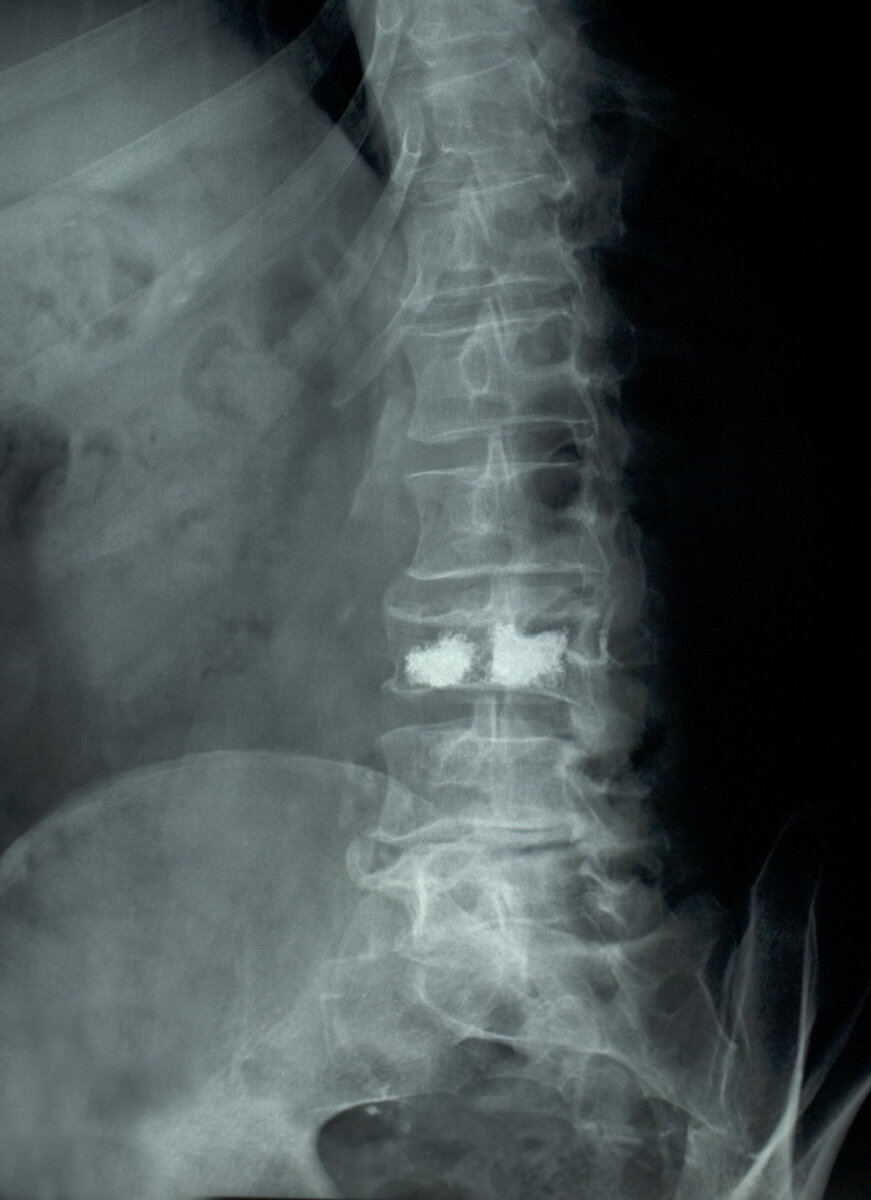

снимок из оригинальной статьи в New York Times

На фото можно видеть рентгеновский снимок, показывающий цемент, введенный в разрушенный поясничный позвонок у 65-летнего пациента. Ученые говорят, что эта процедура, хотя и является обычным делом, не помогает эффективно уменьшить боль.